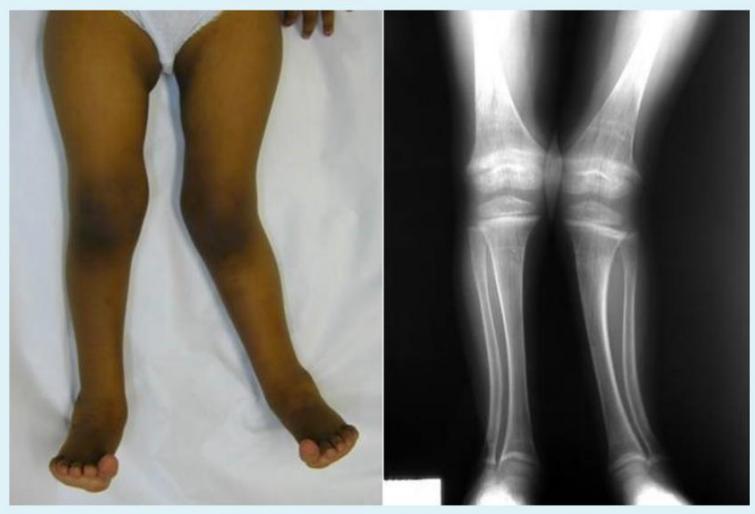

Genu Valgum

Q1: What do you see in this image?

- A. Genu valgum, Coronal view